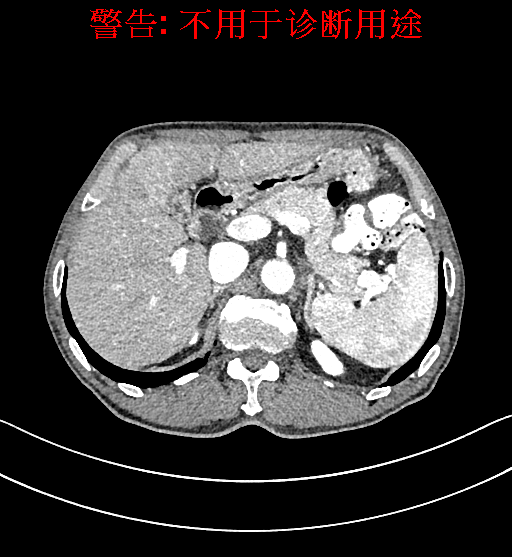

术前CT检查:

平衡期

上腹部动态CT扫描示肝左内叶占位,考虑肝Ca可能性大,请结合临床肝多发小囊肿。

通过调节窗宽窗位调整CT序号,对肿瘤,肝实质,胆囊,下腔静脉,肿瘤,肝动脉、门静脉及肝静脉等进行三维重建;系统自动计算肿瘤体积和肝脏体积。模拟手术操作,自动计算切除肿瘤体积。肝脏体积为1320ml,肿瘤体积为37.88ml,通过比对70-80岁正常肝脏体积为1263.13±170.25 ml,通过术前模拟手术,精准判断切除后剩余肝脏体积能耐受,避免肝衰竭发生。